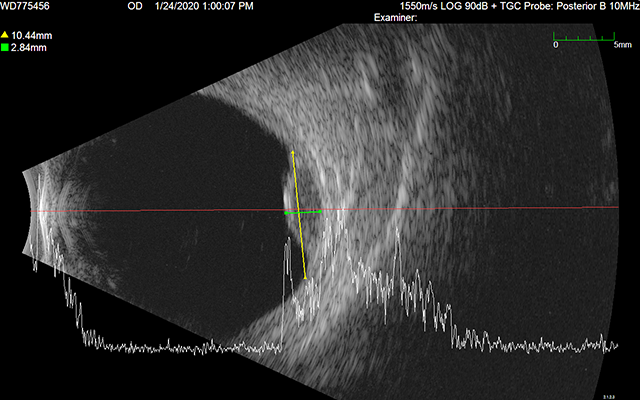

Ultrasound Images

A pair of ultrasound b-scans are used to determine the elevation of the tumor. Ideally, these images should illustrate cross-sections of the longest dimension of the tumor, and a plane perpendicular to that longest dimension. Radial and circumferential cross-sections are also acceptable. Eye tumors are often not clearly visible in CT (or MR) imaging alone. Ultrasound b-scans provided the most accurate measurements and cross-sections of ocular tumors for treatment planning purposes.

US1

US2